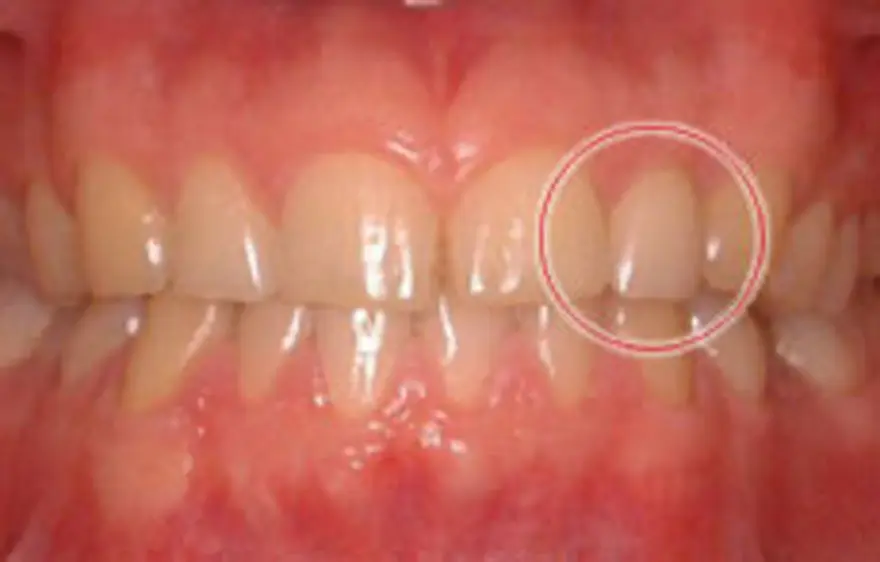

MTM(部分的な矯正)治療例1

飛び出している右の前歯だけ引っ込めたケース

| 患者さまの年齢・性別 | 20代・女性 |

| 治療期間 | 6ヵ月 |

| 治療費(税込) | 352,000円 |

| 主訴 | 右の前歯が前に出ている。 |

| 診断名・主な症状 | 上顎右側中切歯の唇側傾斜をともなう叢生。 |

| 治療に用いた主な装置 | セルフライゲーションブラケット装置(デイモンシステム) |

上顎のみ装置を付け、右の前歯を内側に入れるスペースをつくるため、数本の歯の両端をわずかに削って引っ込めています。歯と歯の間を削る量は決まりがあり、虫歯や歯がしみるなどの原因にならない量を削ります。 |

| 抜歯部位 | 非抜歯 |

| 通院回数・メンテナンス頻度 | 6回 |